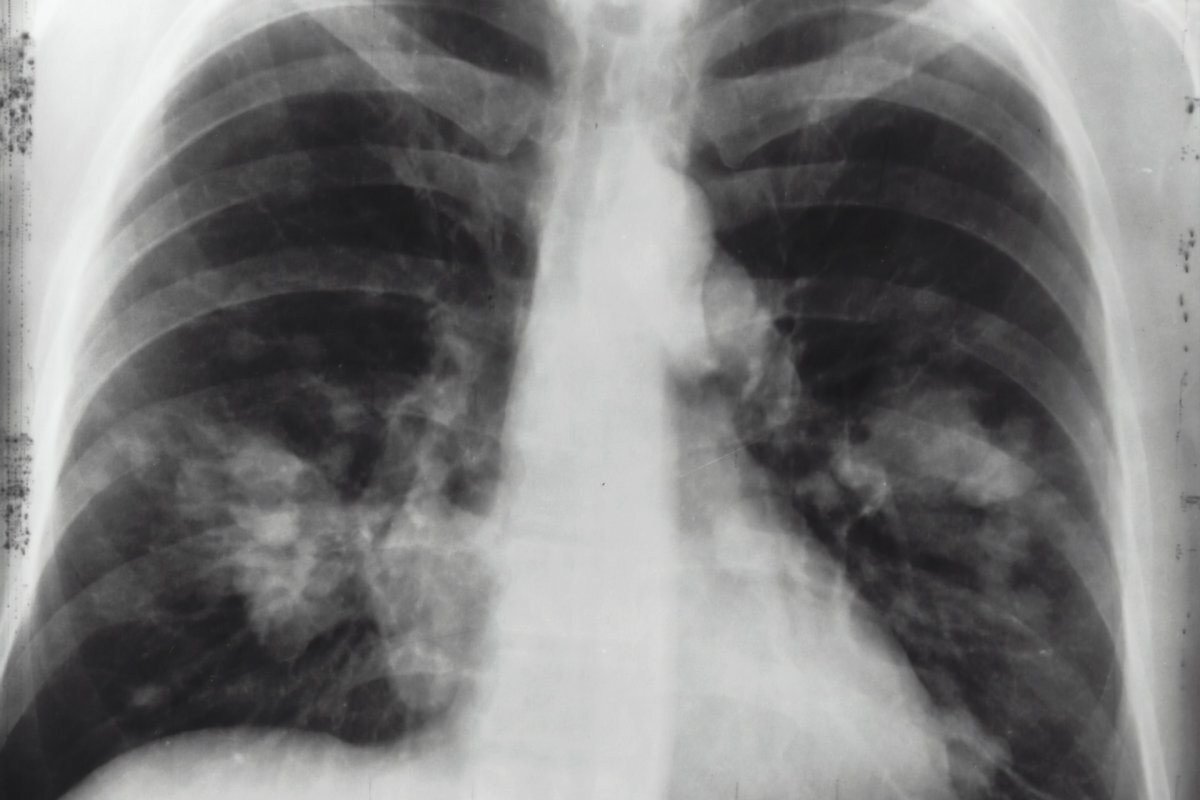

Рак легких является третьим по распространенности видом рака, но на него приходится наибольшее количество смертей от рака. Он также может быстро распространяться по телу, что делает его особенно смертельным. Многие люди знают о том, как болезнь может поражать легкие: среди некоторых симптомов присутствует постоянный кашель и хрипы, однако некоторые признаки могут проявляться и в других местах.

В некоторых случаях изменения на пальцах могут сигнализировать о заболевании. Опухшие пальцы могут быть признаком рака легких.